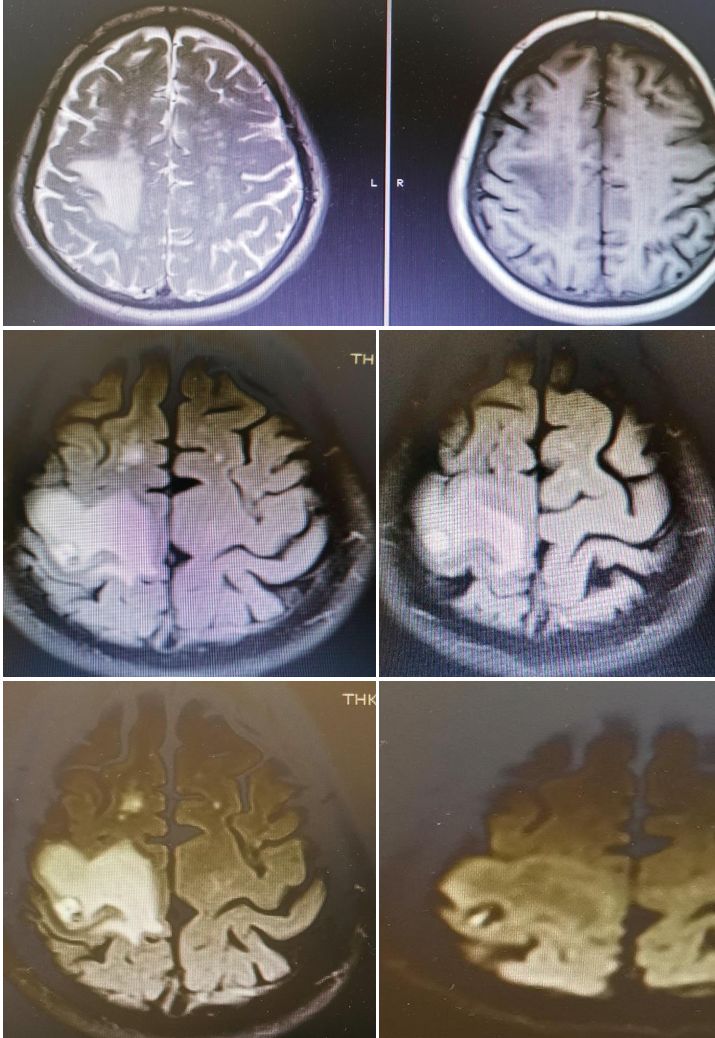

女,36岁,突发意识障碍伴抽搐。

答案:狼疮脑病合并可逆性后部白质脑病综合征(PRES)。补充病史:SLE病史。患者青年女性,有SLE病史,发作性神经系统症状,结合影像学考虑PRES。轻度PRES表现为皮质下或皮质下白质水肿,无实质出血、占位效应、或仅累及脑干或基底节中的一个。中度PRES表现为融合性水肿,从皮质向深部白质延伸,但不延伸至脑室边缘,小脑、脑干或基底节区中有两个轻度受累。重度PRES表现为从皮层到脑室的融合性水肿,或水肿或出血引起中线移位,小脑、脑干或基底节区均受累。

PRES本质上是一种可逆性的血管源性水肿,伴急性神经系统症状,如癫痫发作,脑病,头痛,视觉障碍等。常见原因为:高血压、肾衰竭、使用细胞毒*药性**物、自身免疫性疾病、子痫前期或子痫。约半数PRES患者既往有自身免疫性疾病,如:SLE、血栓性血小板减少性紫癜、甲减、硬皮病、Crohn病、溃疡性结肠炎、类风湿性关节炎、干燥综合征、结节性多动脉炎、肉芽肿性血管炎和视神经血管炎。PRES常由急剧的血压波动或细胞因子对血管壁的直接作用致内皮损伤,引起血脑屏障的破坏,继而引起脑水肿。对称性枕叶皮质下病变要和MELAS鉴别,二者形似神也似。MELAS 的MRI 表现为后部皮层信号改变、脑萎缩、基底节信号改变和钙化、脑白质营养不良。急性期通常会出现 T2 和 FLAIR 高信号,DWI 成像弥散受限。